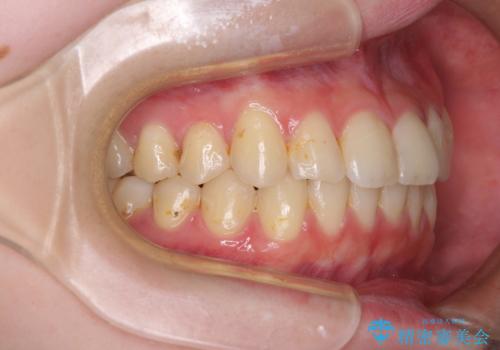

- 上下前歯のデコボコを気にして来院された患者様です。

以前矯正をした後戻りということで、歯列不正はそれほど大きくなかったため、インビザライン・ライトを用いて矯正治療を行うこととしました。

前歯のデコボコが残っており、シミュレーション通りに動いていない部分がありましたが、再矯正であることやご本人の満足いくところまでデコボコが改善されたとのことで、治療を終了することとしました。